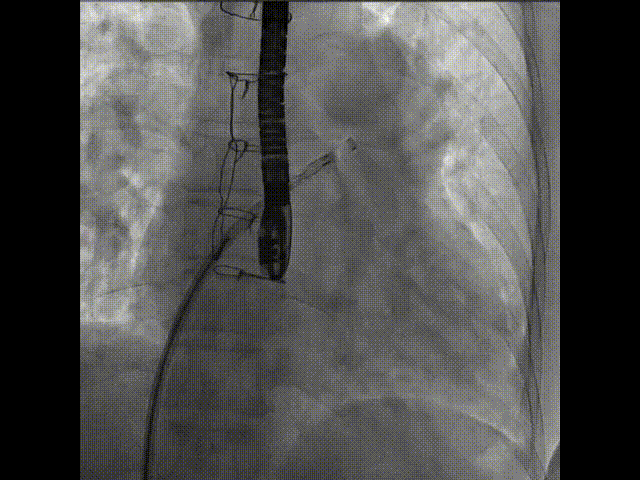

術(shù)中首先在局麻下穿刺股動脈、股靜脈,完成心導(dǎo)管檢查評估后轉(zhuǎn)為全麻,在食道超聲引導(dǎo)下穿刺房間隔,穿刺成功后將加硬導(dǎo)絲送入左上肺靜脈建立軌道,根據(jù)患者病情行球囊預(yù)擴張后植入6mm孔徑房間隔造孔支架,經(jīng)透視及食道超聲評估支架左右盤展開良好,夾持于房間隔兩側(cè),固定穩(wěn)定、位置良好,食道彩超顯示房水平右向左為主分流,分流孔直徑符合預(yù)期大小,心導(dǎo)管檢查評估達到預(yù)期效果,釋放造孔支架。術(shù)后12h患者下床活動,恢復(fù)順利,擬于近日完善術(shù)后評估后出院。